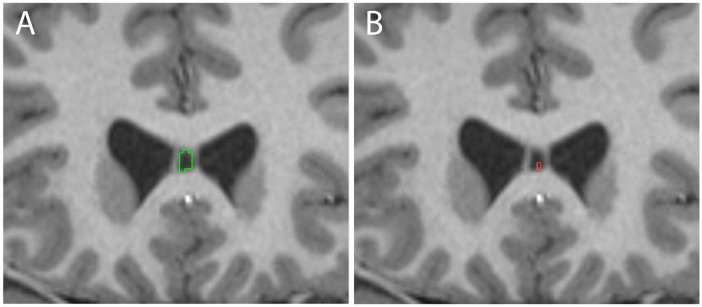

The cavum septum pellucidum (CSP) is a small cerebrospinal fluid-filled space found between the lateral ventricles of the forebrain that is often used as a biomarker for neurological disease and brain injury. The incidence of the CSP varies widely in different studies, with many reports finding that the CSP is frequently absent in healthy brains. Variables such as race, age and sex are typically not well-reported in CSP studies, presenting a challenge to understanding the normal distribution of the CSP in adult human brains. Moreover, the small size and frequently indistinct borders present a challenge for automated segmentation of the CSP. To address these issues, we developed a novel manual parcelation approach to volumetrically segment the CSP in high-resolution T1-weighted structural MRIs from male and female participants in the young adult dataset of the Human Connectome Project (HCP). We identified the CSP in 95.6% of subjects, compared to 57.1% when the automated segmentation approach was used on the same subjects. The CSP volume was significantly larger in male than female brains, both in terms of raw volume and volumes normalized for intracranial volume. To our knowledge, this study is the first to develop and validate a segmentation protocol for CSP volume, and to evaluate both the incidence and volume of the CSP in a representative population of young adults. Overall, these results provide a more accurate representation of the CSP in control populations, laying an improved foundation for its potential use as a biomarker for various disorders.